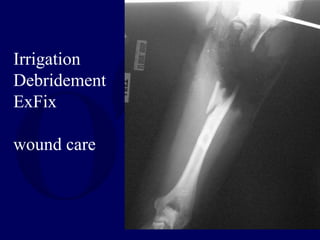

Irrigation

Debridement

ExFix

wound care

• #35 A healthy 29 year old right had dominant woman was injured in an accidental shooting which damaged her left proximal humerus shaft. The pulses and perfusion to the hand were intact, and motor function of all 3 nerves was retained, although there was some weakness of the ulnar innervated muscles.

• #36 She was initially treated with irrigation and debridement and application of an external fixator. Amputation was discussed, but she was adamantly opposed. The wound was treated with dressing changes for a prolonged period.